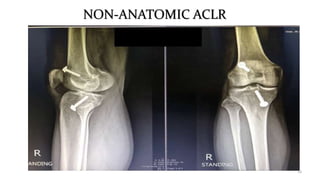

NON-ANATOMIC ACLR

• Traditional ACLRs are placing the graft outside of the native insertion of the

ACL. (clockwise ref.)

• Vertically oriented grafts able to reconstitute stability in the sagittal plane

(anterior-posterior) but fail to provide adequate rotational stability.

• Non-anatomic tunnel placement can alter the forces experienced by the graft

and is one of the main reasons grafts fail (continued instability or re-rupture)

after ACLR.